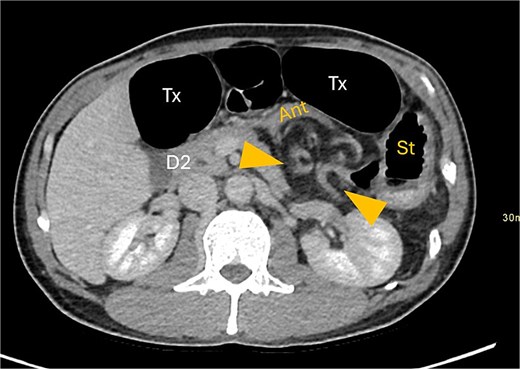

Axial CT image displaying transverse colon in paraduodenal hernia (PDH) with resulting distension of transverse colon (Tx) and stomach (st).

Gastric outflow obstruction of stomach (st) from compression of antrum (ant) by herniated transverse colon. Hernia between arrows.